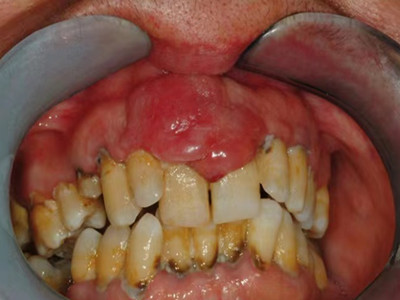

牙龈癌在口腔癌中仅次于舌癌而居第2位,组织学类型绝大多数为分化程度较高的鳞状细胞癌。牙龈癌好发于前磨牙区及磨牙区,下牙龈癌较上牙龈癌为多见,上下之比为2:1。牙龈癌发病年龄多为40-60岁,男性多于女性。

牙龈癌多源于牙间乳头及龈缘区,溃疡呈表浅、淡红,以后可出现增生。由于黏骨膜与牙槽突附着甚紧,较易早期侵犯牙槽突骨膜及骨质,进而出现牙松动,并可发生脱落。X线片可出现恶性肿瘤的破坏特征虫蚀状不规则吸收。

牙龈癌常发生继发感染,肿瘤伴以坏死组织,触之易出血。体积过大时可出现面部肿胀,浸润皮肤。